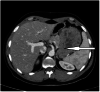

The stomach is the most common site of gastrointestinal stromal tumors (GISTs), representing 60% to 70% of all GIST tumors of the gastrointestinal tract. Gastric GISTs are usually asymptomatic discovered incidentally during endoscopic or radiological investigations. A small percentage may present with melena, hematemesis, and anemia due to recurrent bleeding. We report a case of a giant gastric GIST presented with anemia, that successfully treated with laparoscopic resection.